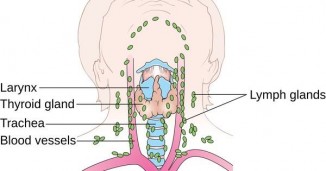

ფარისებრი ჯირკვლის სამკურნალოდ გთავაზობთ რეცეპტებს რომლებიც აუცილებლად გიშველით!

ფარისებრი ჯირკვალი. შეიძლება არსებობდეს ფარისებრი ჯირკვლის გადიდების სხვადასხვა ხარისხი. უკიდურესი, მეოთხე ხარისხია, როდესაც ჩიყვი ჩამოცურდება..